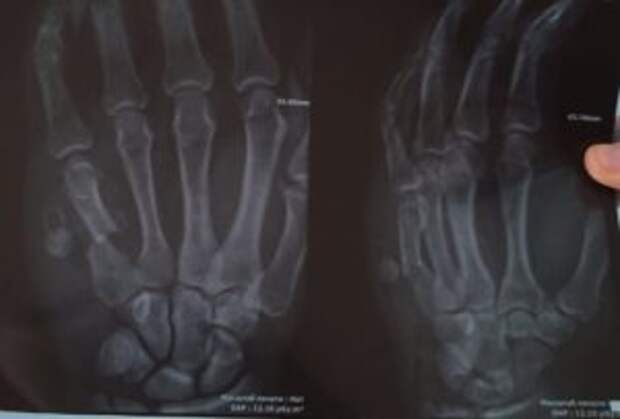

Am Montag, dem 07.03.22, kommt der erste Verletzte zur Behandlung in München an. Hier ist eine Zusammenfassung des Patienten: Diagnose: Schussfraktur des fünften Mittelhandknochens mit Dislokation. Es entstand ein falsches Gelenk, eine Operation ist erforderlich. Aufnehmendes Krankenhaus: Universitätsklinikum Rechts der Isar.

Diagnose: Schussfraktur des fünften Mittelhandknochens mit Dislokation. Es entstand ein falsches Gelenk, eine Operation ist erforderlich.